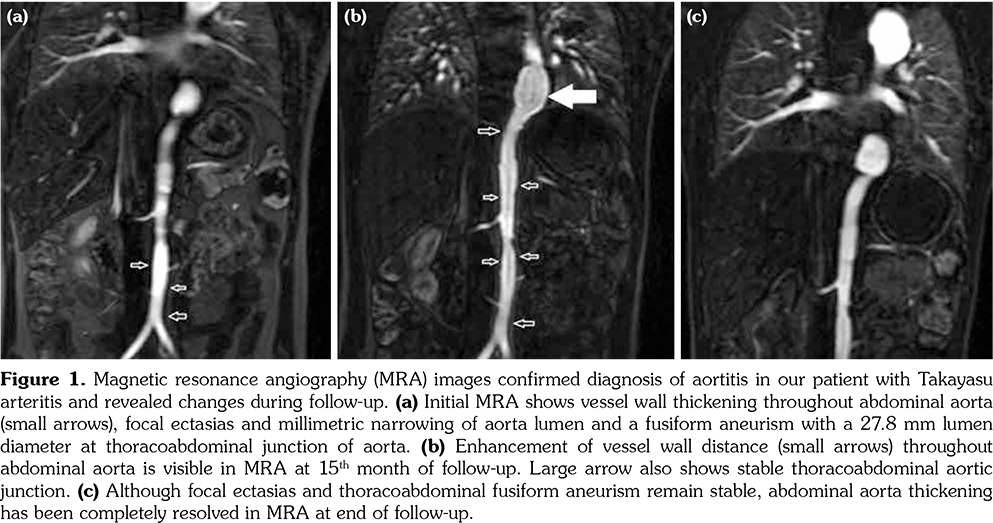

Initial physical examination was normal, including blood pressure and there were no pulse and blood pressure discrepancies among extremities. Acute phase reactants were markedly elevated and autoantibodies were all negative. Viral and bacterial serological markers, interferon- gamma release assay and tuberculin skin test were negative. Abdominal ultrasound, chest X-ray, skin pathergy test and ophthalmological examination were also normal. Renal Doppler ultrasonography revealed diffuse vessel wall thickening and lumen narrowing of renal arteries. Magnetic resonance angiography (MRA) led to the diagnosis of large vessel vasculitis (Figure 1a). Echocardiography also showed vessel wall thickening in the ascendant aorta. Fortunately, carotid Doppler ultrasonography did not reveal stenosis or reduced blood flow, although vessel wall thickening was present in bilateral common carotid arteries.

After TA diagnosis was established, systemic methylprednisolone (2 mg/kg/day) and methotrexate (15 mg/m2 per week) were initiated. Three months later, current therapy did not alleviate the systemic symptoms, so an anti-tumor necrosis factor-alpha agent infliximab (7 mg/kg), was added. After six months, methylprednisolone could be gradually tapered to 0.3 mg/kg per day. One year after the initiation of infliximab, carotid Doppler ultrasonography was repeated due to new onset of carotidynia and revealed diffuse stenosis in bilateral common carotid arteries. Furthermore, MRA showed the fusiform thoracoabdominal aneurysm and progression of abdominal aortitis (Figure 1b). We decided to switch methotrexate to MMF (600 mg/m2/day). Six months later under MMF, infliximab and low-dose of systemic methylprednisolone treatment, MRA showed complete regression of wall thickening in the abdominal aorta (Figure 1c). The laboratory results of the patient were summarized in Table 1.